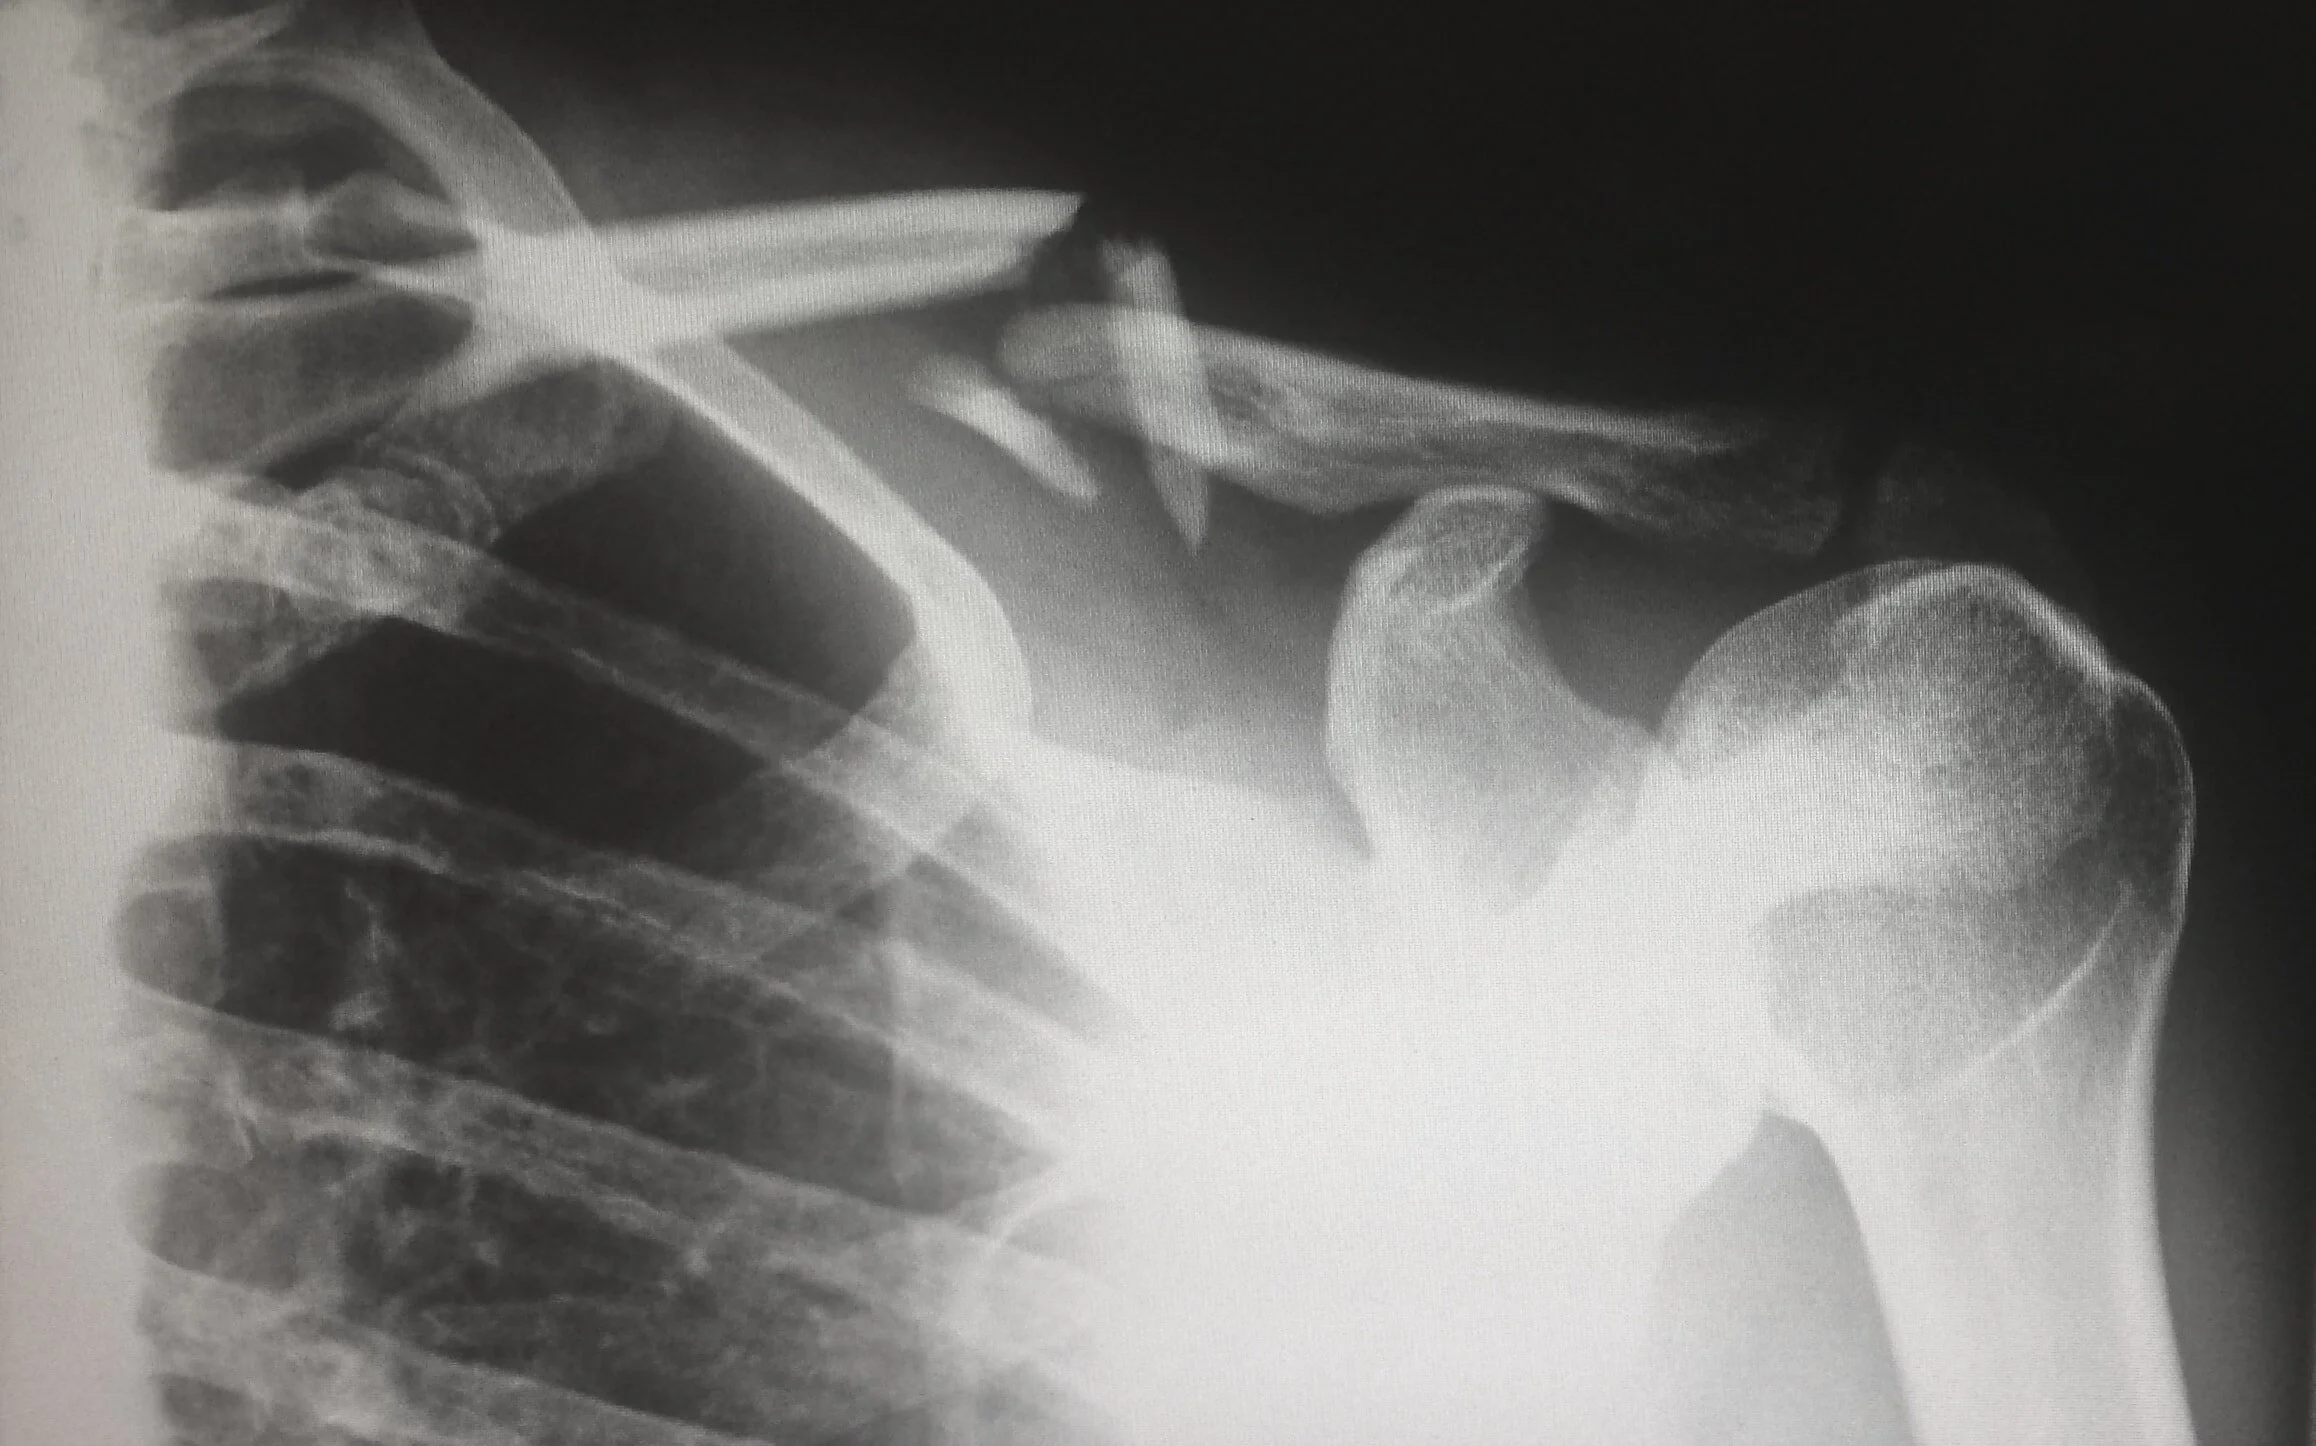

- Radiografieën of X-stralen: De informatie die dit oplevert is vaak beperkt. Op de foto kunnen afwijkingen te zien zijn, terwijl je toch weinig klachten ervaart. Omgekeerd kan de foto er goed uitzien, terwijl je veel pijn hebt. Een radiografie kan soms een vernauwde gewrichtsruimte aantonen ten gevolge van het afslijten van het kraakbeen. Een radiografie kan ook beenderige knobbels aantonen. De kwaliteit van het kraakbeen is echter niet te zien op de foto. Vaak hebben mensen afwijkende radiografieën nog voor er symptomen optreden.